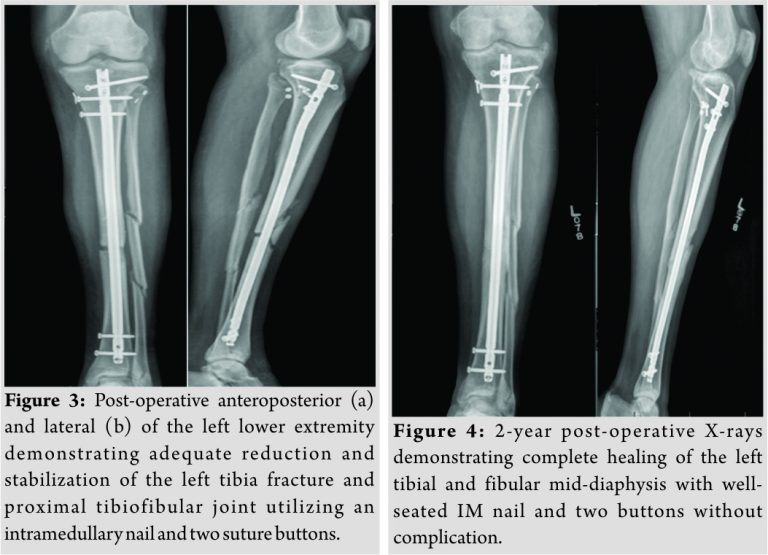

The patient was taken to the operating room with a plan for irrigation and debridement, intramedullary nailing of the tibia and PTFJ reduction and fixation. The patient was placed in a supine position, and the extremity was prepped and draped in a sterile fashion. The open wound was noted medially, and an ellipse-type incision was made to remove the surrounding devitalized skin and provide access to the fracture site. Further dissection revealed the saphenous vein and nerve deep into the wound. These structures were carefully retracted and protected. A curette was used to debride the bone ends, and the wound was subsequently irrigated with 9L of normal saline. The tibia was provisionally realigned using point-to-point clamps. An intramedullary nail was then placed using a suprapatellar approach. The quadricep tendon was found to be intact, and a longitudinal incision was made to obtain access to the joint. A protection sleeve was placed to the proximal tibia, and the guidewire was placed under C-arm guidance. After the guidewire position was confirmed to be adequate, a ball-tipped guidewire with a small distal bend was placed into the canal and extended to the fracture site. Reduction was performed with longitudinal traction andpoint-to-point clamps previously placed at the fracture site. After obtaining satisfactory alignment, the guidewire was further extended to a site just proximal to the physeal scar. An 8-mm cutting reamer was then used to ream the canal, followed by sequential reaming to the appropriately sized nail. The intramedullary nail was then opened and inserted to the proper depth under C-arm guidance. Anteroposterior and lateral films were once again acquired to confirm reduction. Three proximal and 2 distal locking screws were then placed. After the intramedullary nail was secured, the ankle was stressed under fluoroscopic guidance, revealing a stable distal syndesmosis and ankle joint. However, on stressing the proximal syndesmosis with a lateral stress, the proximal fibula demonstrated significant lateral translation and the PTFJ was found to be unstable. A lazy-S incision was made over the proximal fibula and dissection was made down to the PTFJ and proximal fibula, with care taken to avoid injury to the common fibular nerve. The tibiofibular interface was cleaned and a K-wire was placed to achieve proper preliminary alignment. Reduction was confirmed using anteroposterior and lateral images. Two suture buttons were placed through the proximal fibula to the tibia, and the PTFJ was noted to be stable under stress per fluoroscopic evaluation. Images were compared to the contralateral extremity, and reduction was determined to be adequate. All incisions were irrigated with normal saline, a drain was placed in the subcutaneous layer, and the deep, subcutaneous, and skin layers of all incisions were closed. A wound vacuum-assisted closure was placed over the previously ellipsed area of skin at the open portion of the fracture. The patient was then admitted to the hospital and placed in a total range of motion knee immobilizer that was unlocked 0–90°. His compartments were monitored closely postoperatively. He was instructed not to bear weight on the left lower extremity and placed on low-molecular-weight heparin for deep vein thrombosis prophylaxis, and physical therapy was started during hospitalization. He was discharged on the post-operative day 3. He began 25% weight bearing at 6 weeks. Imaging studies immediately postoperatively (Fig. 3) and at 6 months follow-up revealed stable fixation and adequate healing. At 6months, the patient had returned to work, was able to walk without support, and was using a wheelchair only for transporting long distances. At the patient’s 2-year post-operative follow-up appointment, imaging studies demonstrated complete healing of the left mid-tibial and fibular diaphysis with a well-seated intramedullary nail and syndesmotic buttons proximally without evidence of hardware loosening (Fig. 4). At this time, the patient had continued working, walked without support, had a full range of motion, and was neurovascularly intact.

In the case of our patient, a 46-year-old male sustaining comminuted tibial and fibular diaphyseal fractures with a PTFJ dislocation andsuture button fixation achieved successful stability of the PTFJ without evidence of hardware failure at 2-year follow-up. PTFJ dislocations seen in association with tibial shaft fractures have been described [2,8]. PTFJ dislocations are a relatively rare injury and are typically repaired with syndesmotic transfixation screws or tendon reconstruction when they do occur. However, these methodologies have been associated with long-term consequences. Tendon hamstring autografting is known to cause donor site morbidity and potential weakness [9]. In their systematic review, Kruckeberg et al. found a variable return to sport rate using biceps femoris tendon rerouting, with half of the patients returning by 4 months while others required 17 months[10]. Transfixation screw stabilization may be complicated by decreased function and ankle pain due to a less forgiving construct during ankle rotation [5]. Therefore, transfixation screw stabilization often requires subsequent hardware removal, carrying with it the inherent risks of surgery, including surgical site infection and damage to neurovascular structures[2,11]. Here, a novel method of repair using sutures buttons offers promising results. While there does not appear to be literature concerning the use of suture buttons in PTFJ stabilization, there are several studies exploring the biomechanics, efficacy, and long-term results of suture button repair in ankle syndesmosis disruption. Several biomechanical studies have demonstrated adequate ankle syndesmosis fixation and healing with suture button repair [12,13,14]. In addition, there have been many studies demonstrating in vivo efficacy of suture button repair for ankle injuries [11,15]. In one prospective randomized study, malreduction rates were slightly increased with trans-syndesmotic screw fixation in comparison to suture button[15]. Another comparative study showed a superior range of motion with dorsiflexion and plantar flexion at 6- and 12-month follow-up in patients who received suture button repair for ankle syndesmosis injuries [11]. In addition, this study demonstrated the decreased incidence of symptomatic hardware requiring removal with button sutures, which may have significant economic benefits [11]. This type of fixation may also offer a quicker return to work and activity [6].